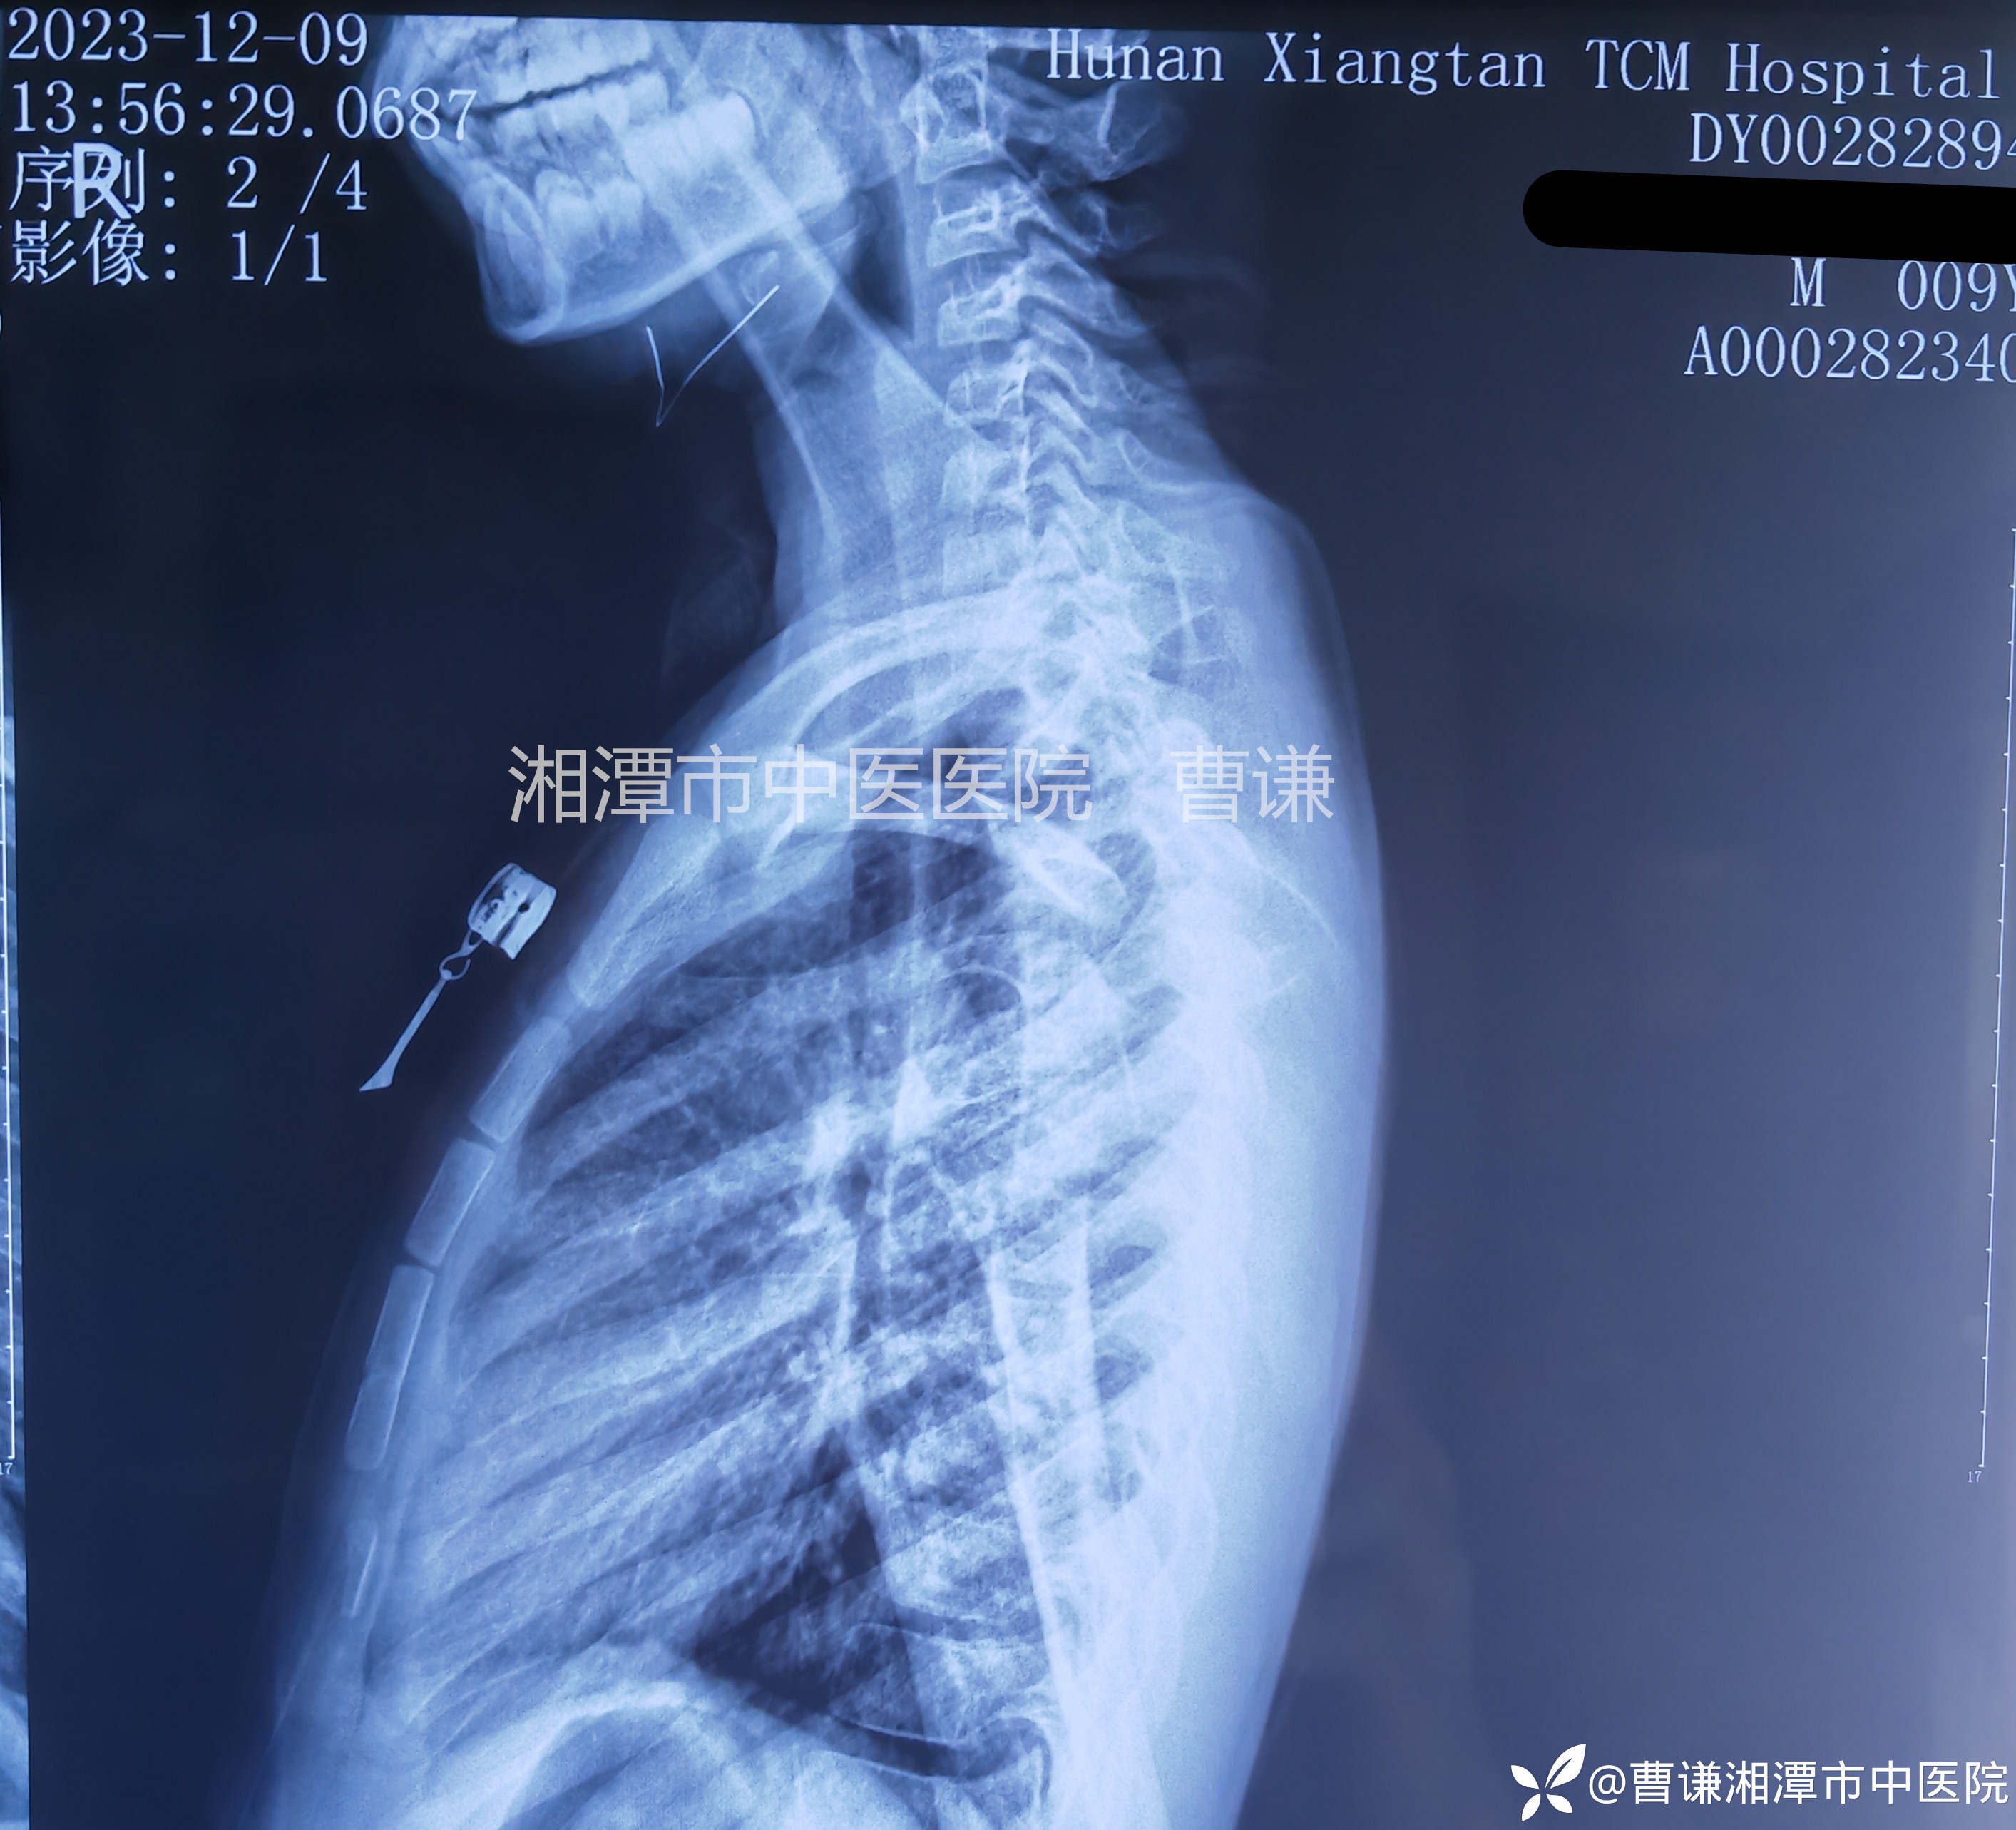

辅助检查:X线片:右肱骨近端骨折,断端错位明显。

患者跌倒致右肩部肿痛,活动受限,就诊于当地医院,拍片示右肱骨近端骨折,初看片子似乎骨折对位良好,其实仔细看可以发现断端重叠明显,虽然拍了两个片子,但其实都是正位,当地医院建议手术治疗,患者家属拒绝手术治疗,转来我院要求保守治疗。

当地医院予以石膏固定转来我院,来我院拍片复查示:远折端向前、向内、向上移位明显,石膏固定显然是无效的,因为患者夜间一直诉疼痛,良好的外固定应该是可以让患者基本无痛的。

固定完成拍片复查见断端仍然完全错位,肩关节还呈现半脱位的改变。管床大夫赶紧拿着片子给我看,估计心里在嘀咕:主任也是多年的老手了,咋整成这样呢?也可能还在想象我老脸一红,一挥手说:“再整一次!”